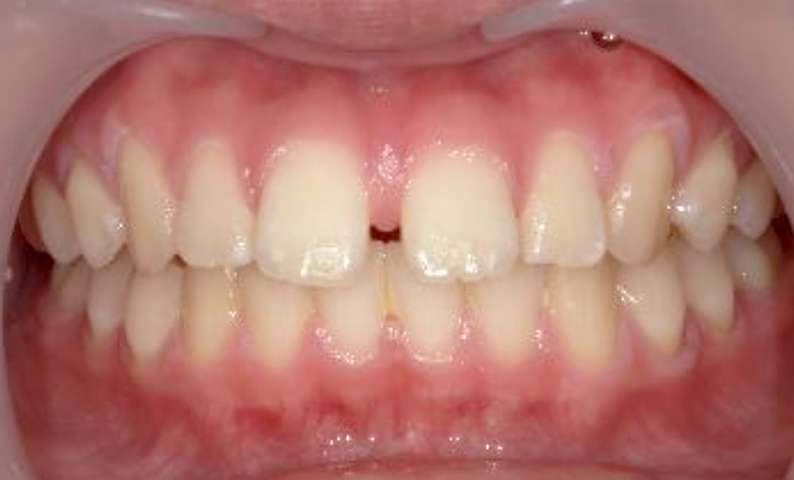

症例_002 上下顎の部分矯正

治療期間:7ヶ月金額:54万円+税女性前歯のガタガタ出っ歯八重歯

| Before | After |

|---|---|

|